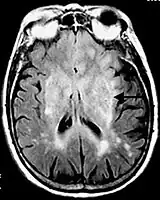

![]() Postcontrast FLAIR of a case of meningitis. It shows enhancement of meninges at the tentorium and in the parietal region, with evidence of dilated ventricles. |

- Meningitis and other leptomeningeal diseases*

* Post-contrast FLAIR images have been added to diagnosis protocol for accurate medical assessment.[2]